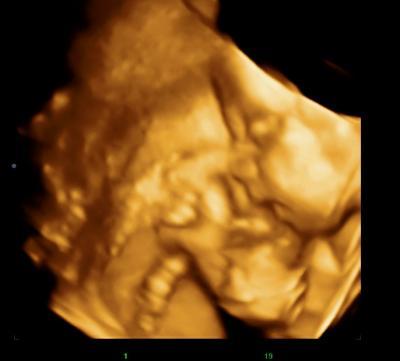

Darf ich vorstellen mein Sohnemann

Bild zu